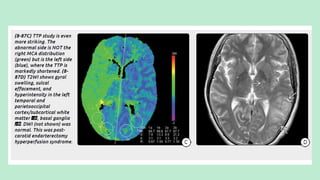

IMAGING

NECT scan: May show only mild gyral swelling.

CTA/pCT: Show congested, dilated vessels with elevated blood flow and

decreased MTT/TTP

MR Findings:T2/FLAIR scans show gyral swelling, hyperintensity, and

sulcal effacement in the internal carotid distribution.

T1 C+ scans may be normal or show mildly increased intravascular

enhancement.

DWI is typically negative, as the edema is vasogenic rather than cytotoxic.

pMR shows elevated CBF and cerebral blood volume with decreased

(shortened) MTT.

Postprocedure CHS on TOF-MRA is seen as an increase in the

change ratio of signal intensity more than 1.5x the preoperative level.

Nuclear Medicine: Single-photon emission computed tomography

(SPECT) has demonstrated focal hyperperfusion at the

revascularization